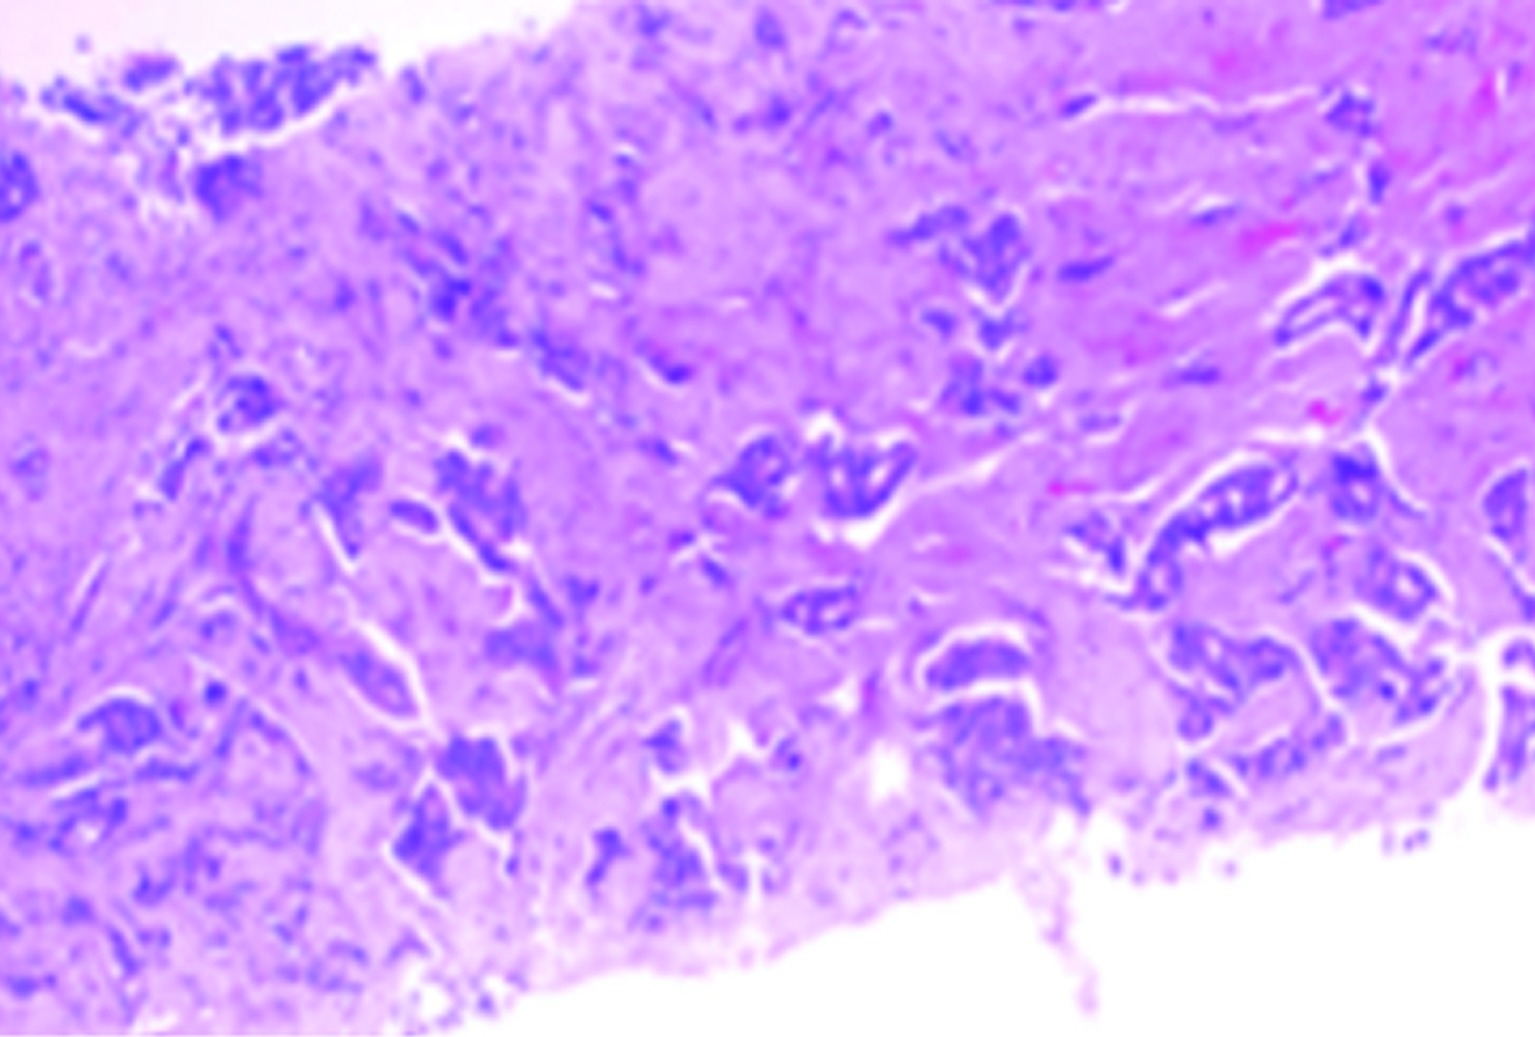

戈沙妥珠单抗于2022年6月正式被国家药品监督管理局批准上市,作为作用于Trop-2靶点的抗体偶联药物,为晚期三阴性乳腺癌患者带来了新的治疗选择。现报道1例晚期三阴性乳腺癌患者在病情出现进展时使用戈沙妥珠单抗治疗后情况,病情变化达到稳定,患者获益较为明显。